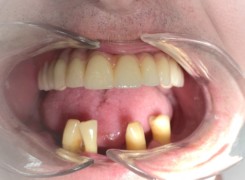

Pan Ryszard trafił do Naszego Gabinetu z jasno sprecyzowanym oczekiwaniem. Miał 84 lata i chciał odzyskać możliwość swobodnego spożywania posiłków oraz poprawienia sobie komfortu życia a także prosił aby przywrócić mu piękny uśmiech jakim cieszył się przed laty. Już na początku pierwszej rozmowy zastrzegł, że interesuje go wyłączenie rozwiązanie uzupełnieniem protetycznym stałym. Nie miał zamiaru użytkować żadnych protez ruchomych. Mając na uwadze powyższe wykonaliśmy Panu Ryszardowi zdjęcie pantomograficzne oraz badanie tomograficzne szczęki i żuchwy na postawie których zapanowywaliśmy Pacjentowi optymalne rozwiązanie – stałe uzupełnienie protetyczne w postaci 28 koron cyrkonowych zamontowanych do dwóch belek cyrkonowych które będą przymocowane do 16 implantów w konfiguracji 8 wszczepów w szczęcie 8 w żuchwie. Po omówieniu powyższego planu przystąpiliśmy do Wspólnej pracy której efekty w poszczególnych etapach prezentujemy poniżej.